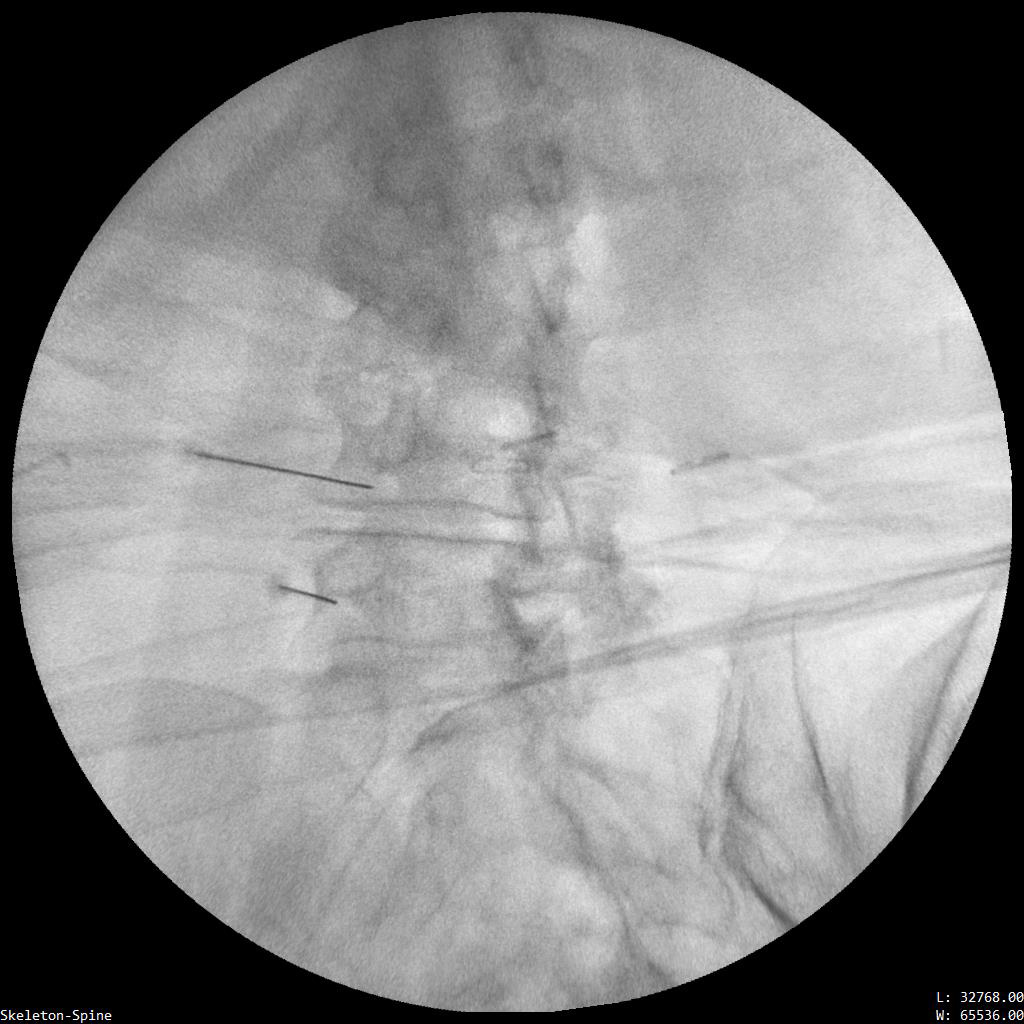

Ασθενής με 2 δισκοκήλες

Aσθενής 35 ετών με έντονο άλγος οσφύος από 4μήνου και αντανάκλαση στο κάτω άκρο λόγω 2 δισκοκηλών σε 2 επίπεδα. Με τοπική αναισθησία τοποθέτηση 2 βελόνων στα σημεία πίεσης των νεύρων. Έλεγχος σωστής τοποθέτησης με χρήση σκιαστικού και εισαγωγή μείγματος αναλγητικών. Άμεση ανακούφιση με αποτέλεσμα που διατηρείται 6 μήνες μετά.